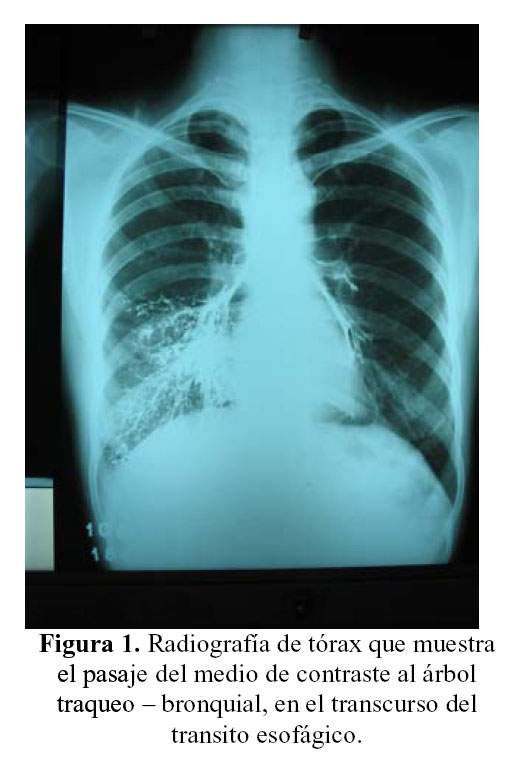

Las radiografías de esófago con doble contraste, revelaron abundante pasaje del contraste al árbol bronquial (Figura 1), indicando la presencia de una fístula probablemente con la tráquea. Además en la tomografía computada del cuello se observa la presencia de enfisema subcutáneo (Figura 2). Si bien la causa neoplásica más frecuente de fístulas tráqueo esofágicas es el cáncer de esófago (1), esta entidad produce esta complicación con poca frecuencia (2,3). También ocurren fístulas directas entre esófago y pulmón que son muy raras, así como fístulas esófago bronquiales; pero generalmente el cáncer de esófago se localiza en su tercio medio dando las fístulas traqueo-esofágicas.